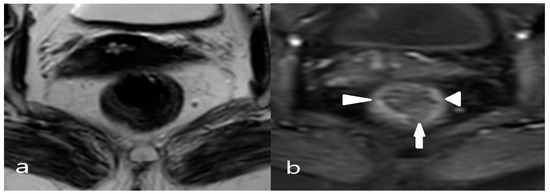

2.5. Anatomical Classification of Lateral Lymph Nodes and Classification of Pathological Lymph Nodes Based on Size